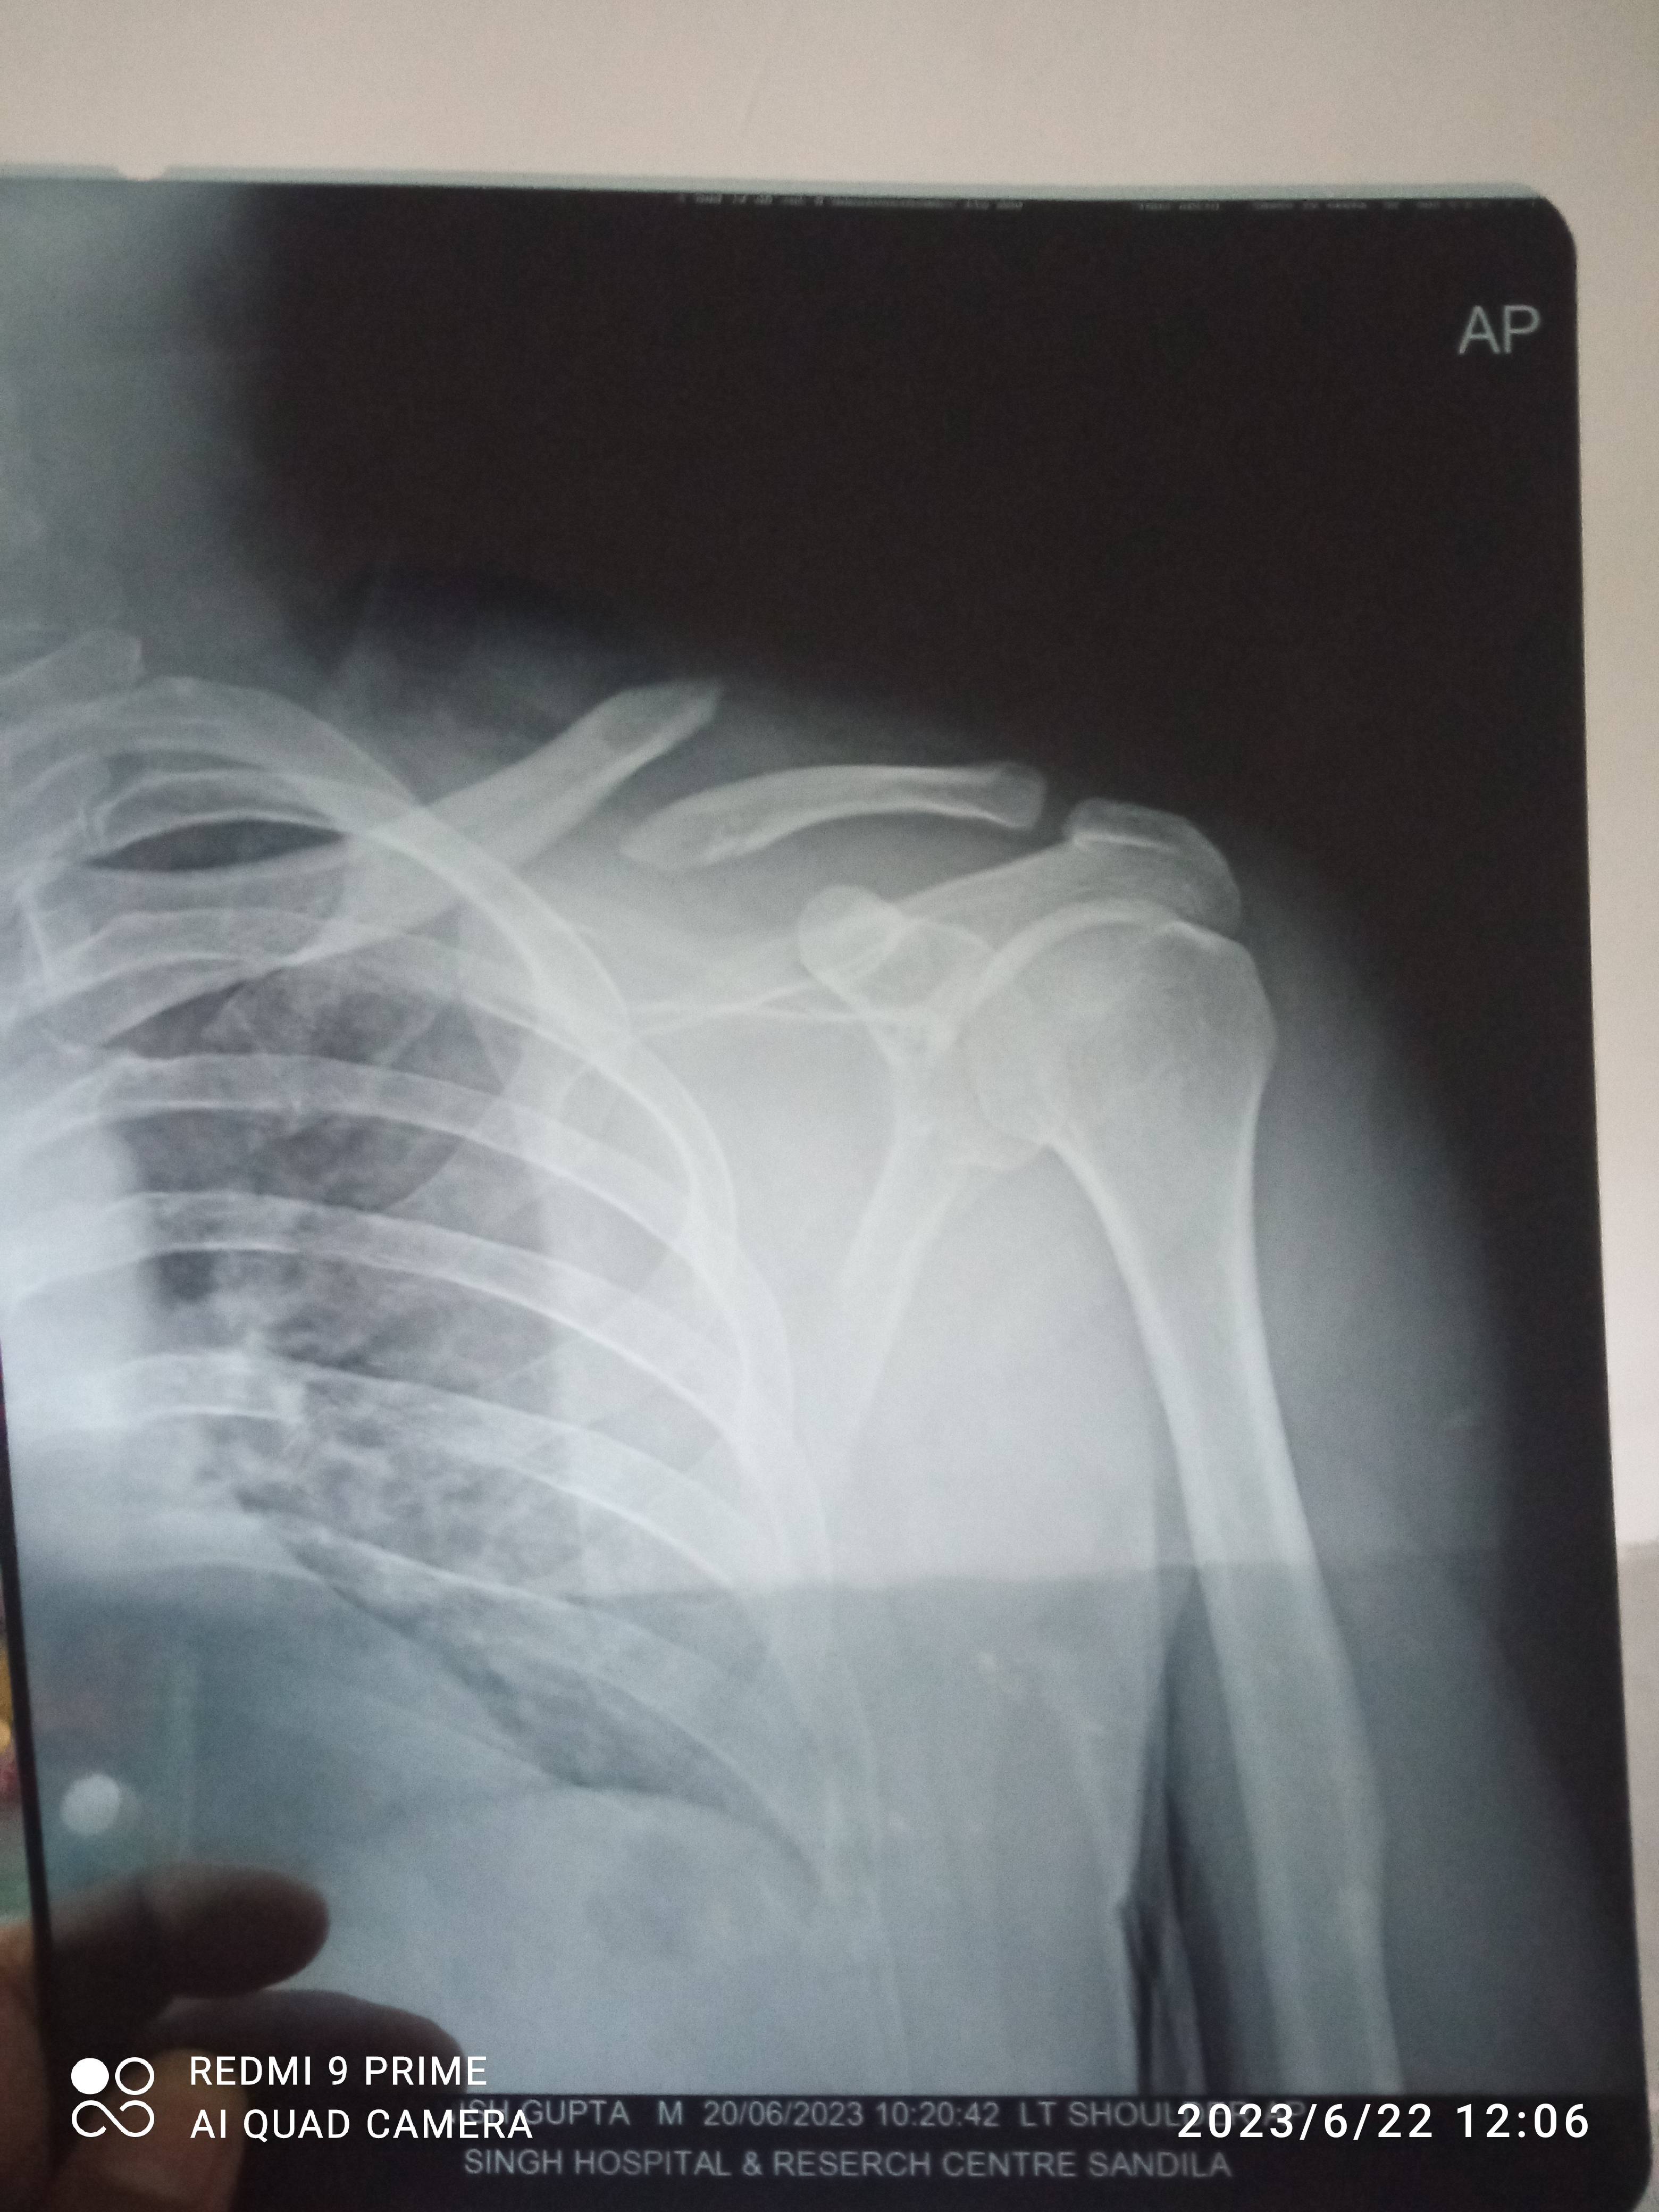

Sir doctor has prescribed 8 type neck band. Will it heal without operation?? How much time it Will take. I am 31 yrs old.

Cycercial facture

Need any operation